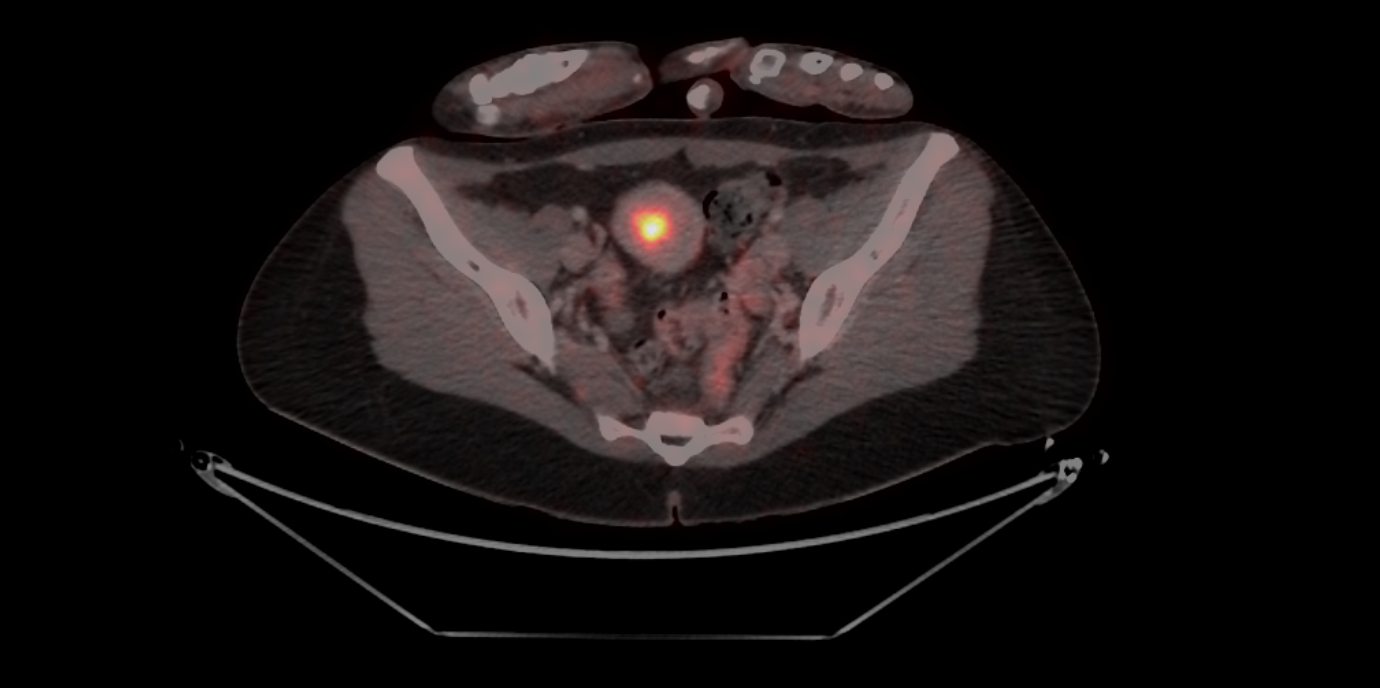

Das Endometriumkarzinom (Gebärmutterkörperkrebs) ist die häufigste Krebserkrankung der weiblichen Genitalorgane und im frühen Stadium gut behandelbar. Die Herausforderung liegt im fortgeschrittenen Stadium (III und IV) und bei wiederkehrender Erkrankung, eine platinhaltige Chemotherapie ist hier das Mittel der Wahl. Gynäkologische Forschungsbestrebungen gehen dahin, die wirksame, aber belastende Chemotherapie durch neue Immun- und Kombinationstherapien zu unterstützen oder zu ersetzen.

*) Die Klassifizierung des Tumors erfolgt u.a. auch nach histologischen und molekularen Methoden. Das Bestimmen des MMR-Status (mismatch-repair; Mutationen, die die DNA-Reparatur betreffen) mittels Immunhistochemie kann eine entscheidende Relevanz für die Therapieplanung beim lokal fortgeschrittenen und/oder rezidivierten Endometriumkarzinom haben. pMMR = Mismatch-Repair-profizient, dMMR = Mismatch-Repair-defizient.(27.11.2024, Text: D. Heidegger, Bild: Univ.-Klinik für Nuklearmedizin Innsbruck/Rossetti)